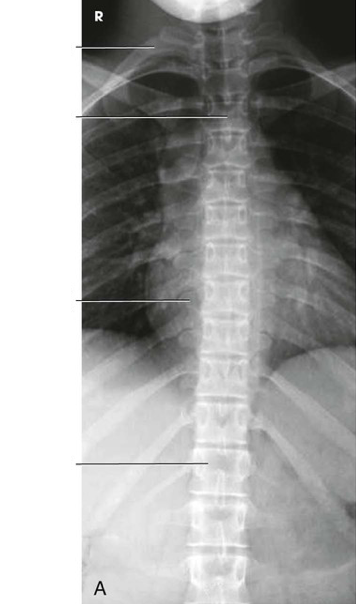

Question 4

Question

Label the image

Image:

Answer

C3

C6

intervertebral foramen

pedicle

intervertebral disk space

first rib